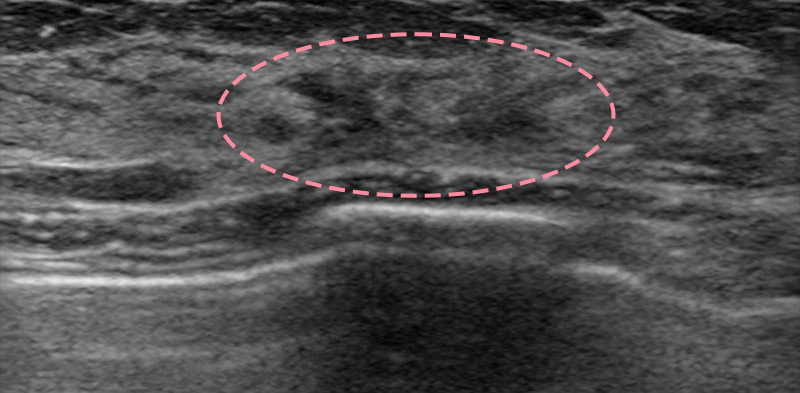

보형물 가슴성형 후 제법 크기가 있는 종양이 발견된 사례입니다.

가슴성형 후 맘모톰시술은 보형물의 위치를 파악하면서 바늘을 다루어야 하기 때문에 고도의 숙련도와 정밀한 판독 능력이 필요합니다.

한송이 원장은 다양한 사례를 접해온 경험과 전문성을 바탕으로 시술을 성공적으로 마쳤습니다.

총조직검사 후 최종 진단 결과 양성 종양(섬유선종)으로 확인되어 맘모톰 시술로 제거를 진행했습니다. 7개월 경과 후 검사를 통해 인공 보형물의 누수 및 파손 없이 깨끗한 내부 상태가 확인되었습니다.